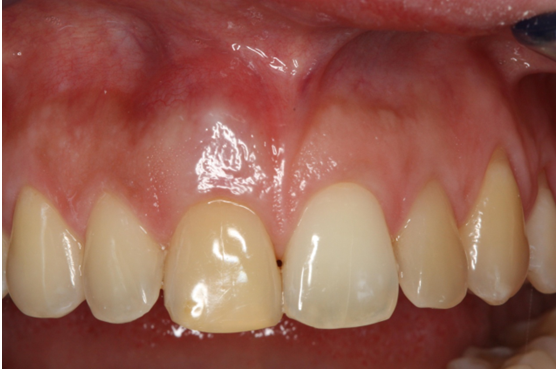

4. Εμφυτεύματα στην αισθητική ζώνη

Τοποθέτηση εμφυτεύματος στην πρόσθια (αισθητική) ζώνη. Ασθενής ετών 30 προσήλθε στο ιατρείο παραπονούμενη για πόνο, οίδημα και πυορροή στον κεντρικό τομέα άνω δεξιά.

Το δόντι είχε κακή πρόγνωση (κάταγμα ρίζας) και για το λόγο αυτό έγινε εξαγωγή και ταυτόχρονα δημιουργία νέου οστού με τοποθέτηση μοσχεύματος και μεμβράνης (οστική ανάπλαση). Μεθύστερα, τοποθετήθηκε εμφύτευμα και η επούλωση κρίθηκε απολύτως επιτυχής.

ΑΡΧΙΚΗ ΚΛΙΝΙΚΗ ΕΙΚΟΝΑ

ΧΑΜΟΓΕΛΟ ΑΣΘΕΝΟΥΣ (ΑΡΧΙΚΗ ΕΙΚΟΝΑ)

ΕΠΟΥΛΩΣΗ ΜΕΤΑ ΤΗΝ ΑΝΑΠΛΑΣΗ

ΤΕΛΙΚΗ ΕΙΚΟΝΑ ΑΣΘΕΝΟΥΣ (3 ΜΗΝΕΣ ΜΕΤΑ)